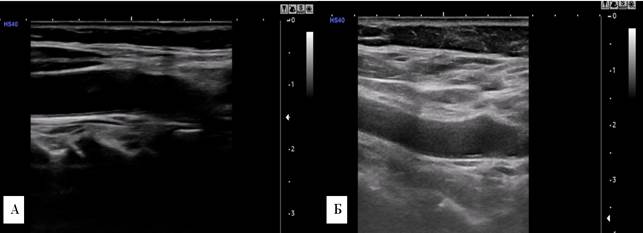

У женщин 36-55 лет длина a. сarotis communis dextra была равна 64,8±1,4 мм, длина a. carotis communis sinistra составляла 63,5±1,8 мм, что меньше аналогичных показателей у женщин 20-35 лет. Диаметр a. carotis communis dextra et sinistra был равен 6,6±0,08 мм справа и 6,7±0,02 мм слева, толщина интима-медиа a. carotis communis dextra составляла 0,67±0,02 мм, a. carotis communis sinistra 0,65±0,03 мм, что больше, чем соответствующие показатели в возрастной группе 20-35 лет (рис. 2).

Рис. 2. Сонограмма a. carotis communis dextra. А – мужчина, 37 лет; Б – женщина, 39 лет.

У мужчины диаметр артерии больше